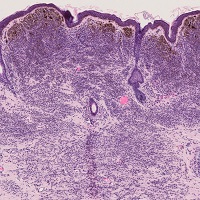

尋常性乾癬